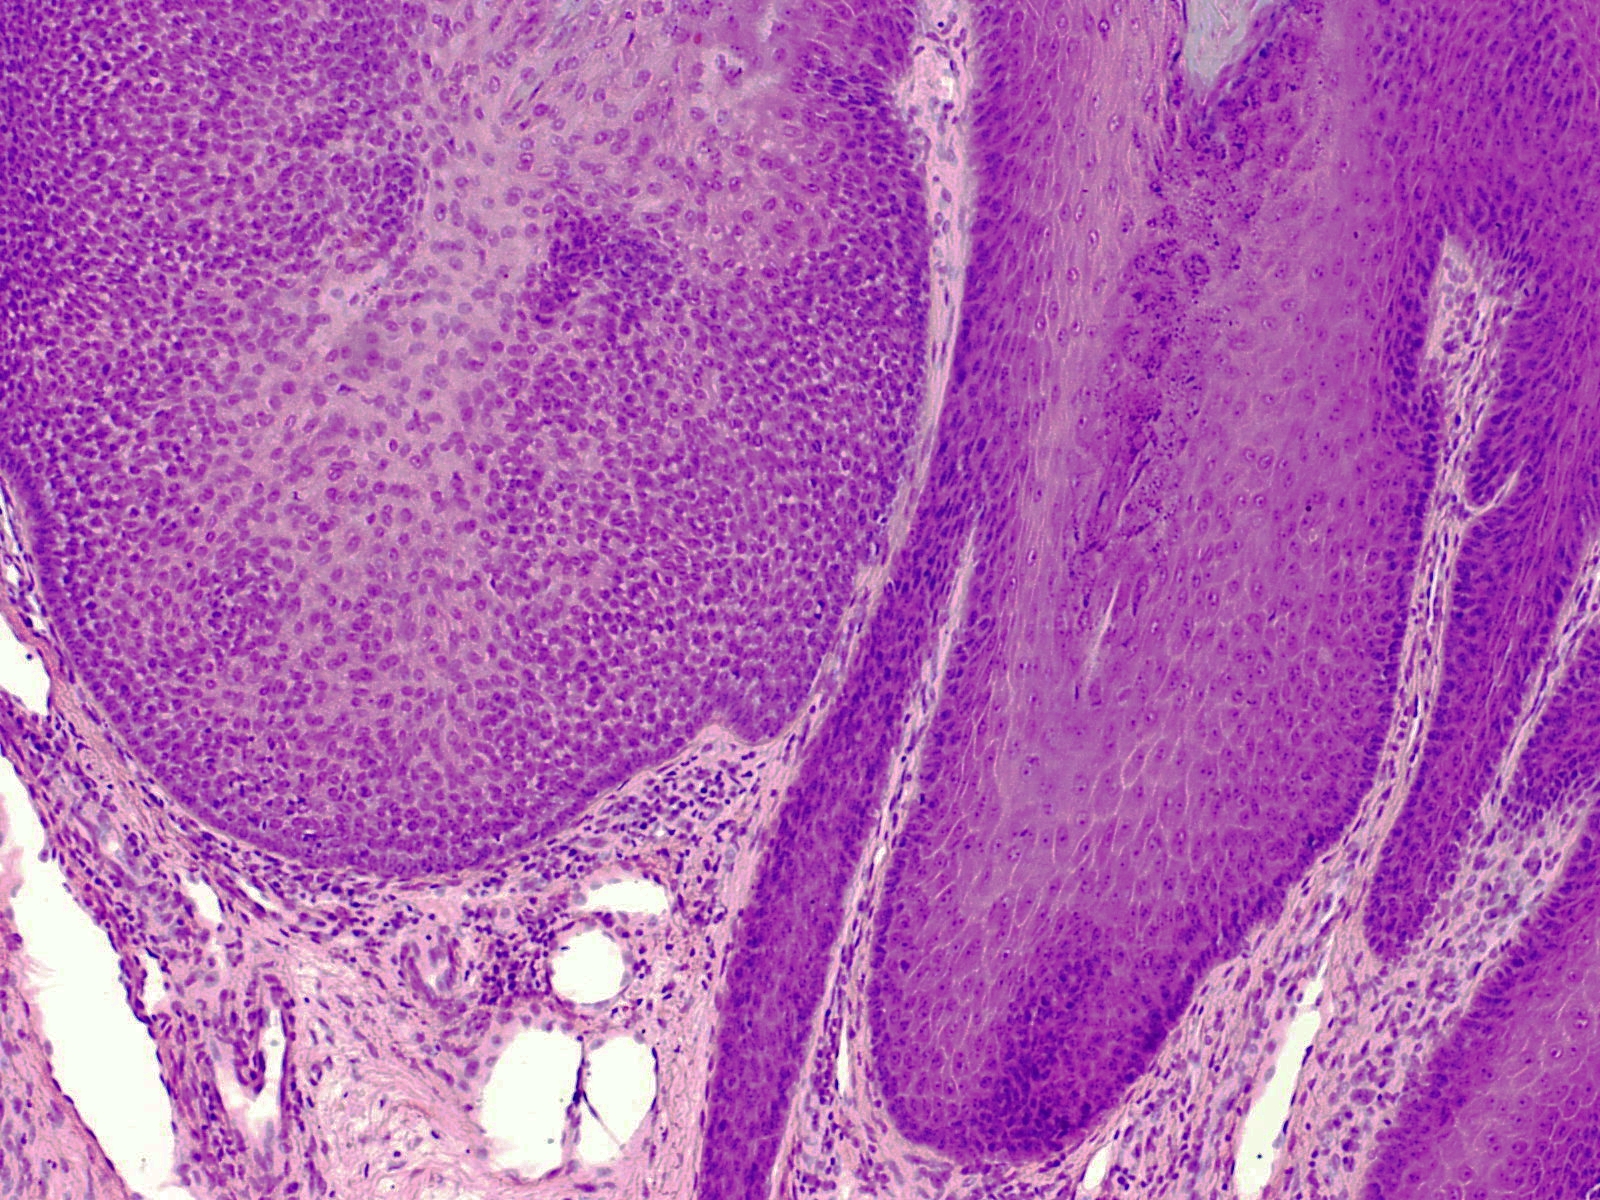

PA:Goed afgrensbaar vaak rond, lobulair tumortje opgebouwd uit plaveiselcellen zonder atypie. In verbinding met de epidermis. Meestal met hyperkeratose. De cellen kunnen basaloid aankleuren waardoor het kan lijken op een basaalcelcarcinoom. Er is ook randpallisadering, met cuboidale of columnar cellen op een duidelijk zichtbare basaalmembraan, waarbij de celkernen hoog kunnen liggen (reverse polarity). Andere componenten die gezien kunnen worden bleke eosinofiele cellen, clear cells, desmoplasie, squamous morules (squamous eddies), en centraal mucine depositie.

PA-Foto's:

L. Wozniak en K.W. Zielinski - Wikimedia (Creative Commons license

3.0).